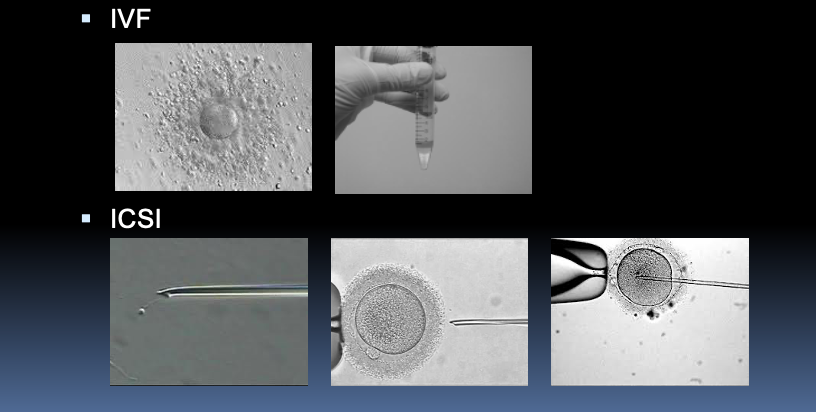

treatments offered to men with abnormal semen parameters?

A

-Intrauterine insemination (IUI)

-In vitro fertilisation (IVF)

-Intracytoplasmic sperm injection (ICSI)